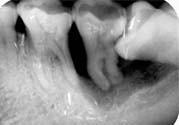

5、如果智齒經(jīng)常疼,而且疼的比較厲害,可能已經(jīng)引發(fā)牙冠周軟組織發(fā)炎,所以導(dǎo)致智齒腫脹、疼痛;再如果智齒長的位置很歪,影響其它牙齒正常咀嚼,也影響美觀,最好是考慮拔牙。拔牙前提是確保牙冠周圍沒有炎癥,才能安排拔牙,免除后顧之憂,拔智齒是拔牙里最難的一種,所以一定要到正規(guī)口腔醫(yī)院,請正規(guī)醫(yī)師進(jìn)行專業(yè)拔牙。

1、冠周炎:智齒因阻生而使牙冠不能完全外露,牙冠周圍的牙齦成袋狀,極易積存食物、滋養(yǎng)細(xì)菌。當(dāng)全身抵抗力下降時(shí)引起急性冠周炎。

3、第二磨牙齲壞:向前傾斜的阻生智齒,因經(jīng)常在鄰牙間積存食物,易發(fā)生鄰牙(下頜第二磨牙)齲壞。